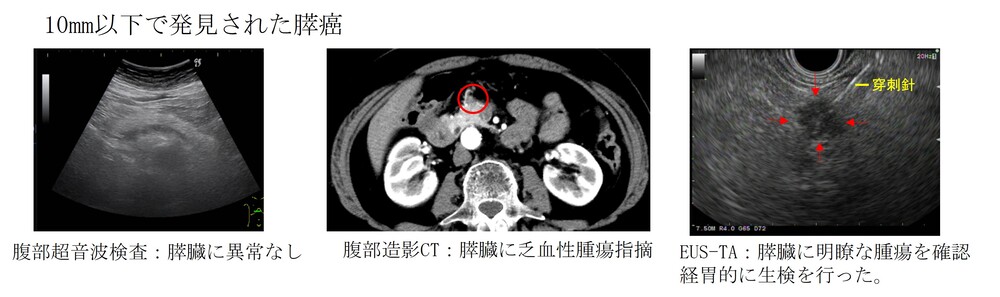

膵臓の酵素や腫瘍マーカー(がんの可能性を調べる血液検査)に異常があったり、お腹の症状や超音波検査で気になる点が見つかった場合は、より詳しく調べるためにCTやMRI検査を行います。

一般に胆道がんや膵がんは、早い段階で見つけるのが難しい病気です。そのため、CTやMRIで異常が見つかった場合には、さらに詳しく調べるために「超音波内視鏡(EUS)」や「内視鏡的逆行性胆管膵管造影検査(ERCP)」という検査を行います。

さらに、必要に応じて、超音波内視鏡(EUS)を使って腫瘍の細胞を採取する検査(超音波内視鏡下組織採取/EUS-TA)や、ERCPを使って組織を採取する検査(生検や擦過細胞診)を行い、がんかどうかを確定します。